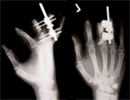

Digit lengthening in a 23 years old industrial worker

Traumatic Amputation of middle three fingers left hand at level of middle phalanx with terminilisation done